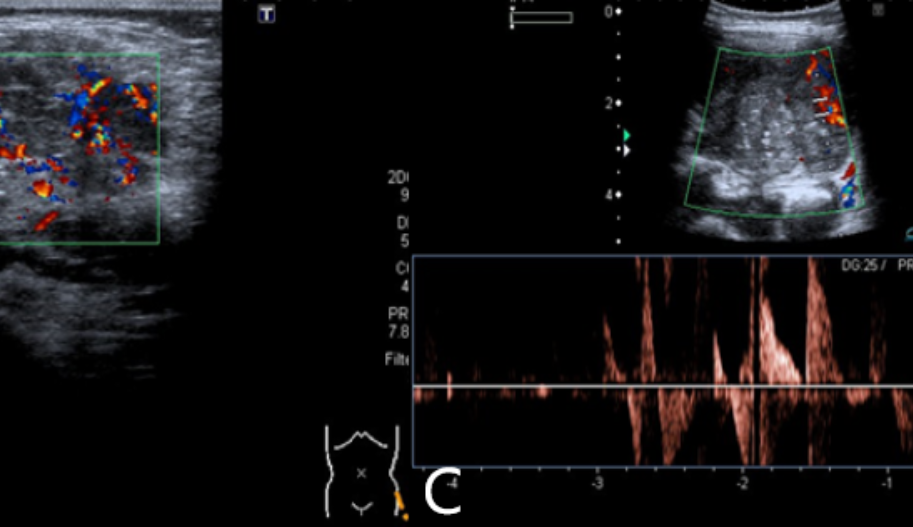

Kitle lezyonu renkli Doppler

Kötü huylu tümörlerin büyümesi büyük ölçüde yeni damarlar tarafından sağlanan kan temini üzerine tümör anjiyojenik uyarısı altında gelişir. Bu yeni damarlar lezyona nüfuz eder.

Tümör içindeki seyri ve dağılımı kaotik ve düzensizdir ve birden fazla anastomoz ve şant bulunur. Bu damarların düzensiz seyri, renkli dopplerde anormal akışları ile tanımlanırken,

yüksek hız ve/veya düşük dirençli, dalga formu analizi ile tespit edilebilir.

Yumuşak dokulardan kaynaklanan habis tümörlerde de anormal akış tanımlanmıştır.

Doppler ultrason cihazları kan akışının varlığı ve tanımlama yeteneği konusunda yüksek hassasiyete sahiptir.